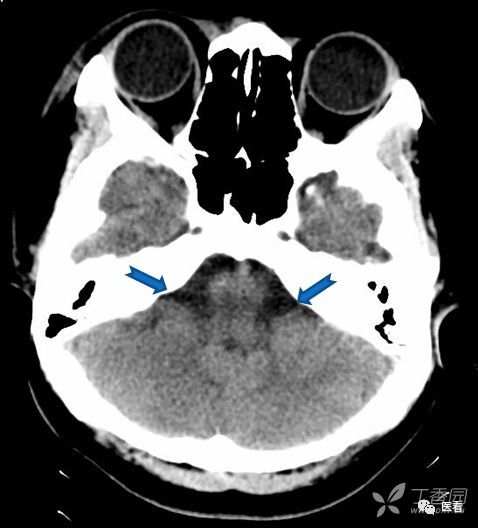

亨氏暗区

颅底(致密)骨产生的横行或放射状伪影,与设备性能也有关系

下图为16拍MSCT,伪影较轻。

此图为双排螺旋 CT图像, 伪影较16层及以上MSCT显著的多。